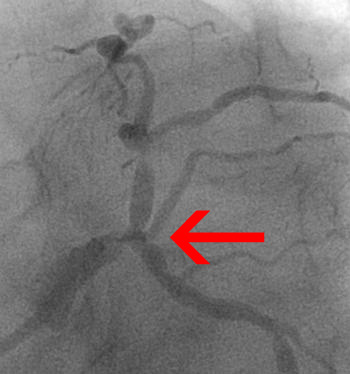

If serial stenoses are less than 3 vessel reference diameters apart, they should be scored as one lesion. However, stenoses at a greater distance from each other (more than 3 vessel reference diameters), are considered as separate lesions.

* ≥3 vessel reference diameters.

This case should be described as

two lesions:

- one lesion involving segments 5, 6, and 11 and

- one lesion involving segment 6.